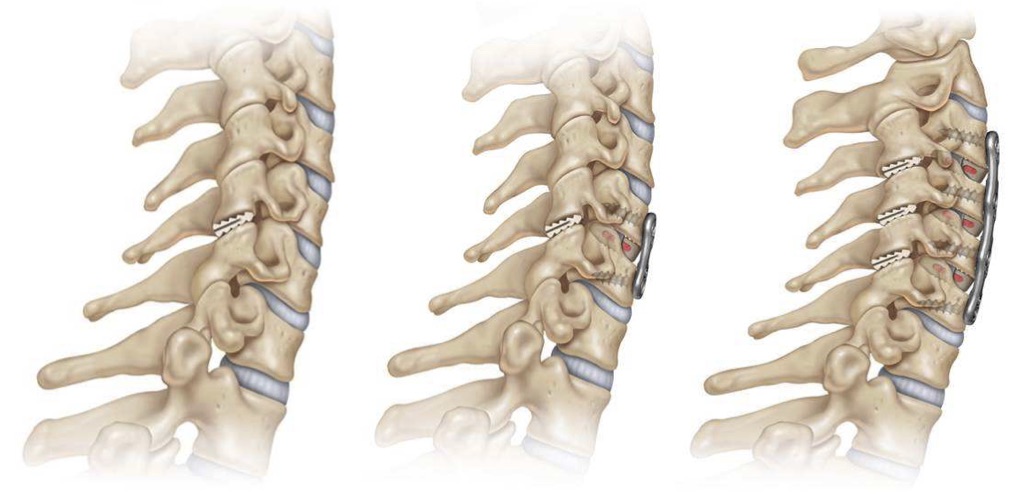

El sistema DTRAX® se compone de 2 cuñas de titanio que se introducen entre las facetas articulares cervicales para conseguir un aumento del espacio foraminal produciendo así la descompresión de la raíz o raíces nerviosas comprimidas a través de la distracción facetaria a la vez que produce una fijación estable de la articulación en el nivel implantado favoreciendo la fusión. Todo ello se realiza mediante un abordaje mínimamente invasivo gracias a un instrumental especialmente diseñado para ello.

DTRAX® está indicado para su uso en pacientes esqueléticamente maduros con patología degenerativa discal de la columna cervical (C3 a C7) con acompañamiento de radiculopatía y/o dolor facetario. La distracción facetaria que produce el DTRAX® hace que el espacio foraminal aumente aproximadamente en un 20% además de producir una estabilización de la articulación mayor en movimientos de rotación axial y movimientos laterales e igual en flexo- extensión si lo comparamos con la estabilización que produce una caja y una placa colocada mediante un abordaje anterior tradicional.